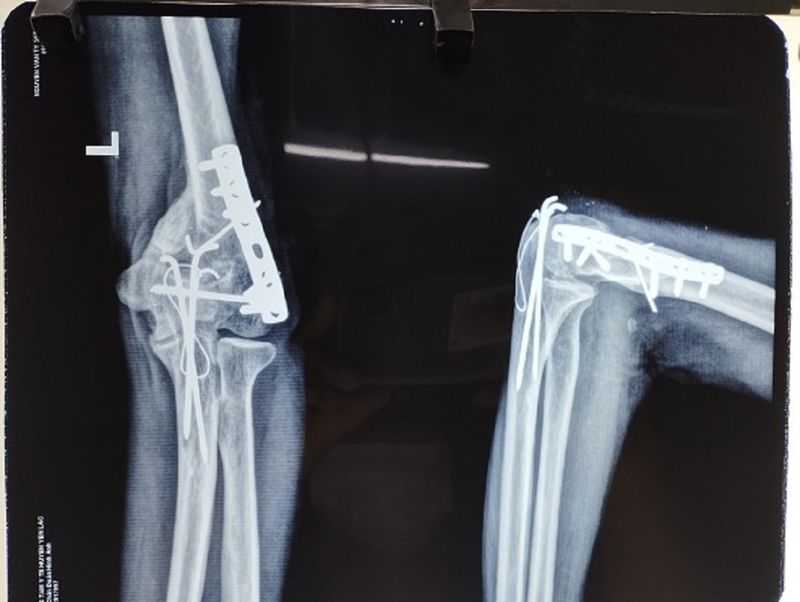

Phương pháp phẫu thuật kết hợp xương là một phương tiện phổ biến hiện nay để điều trị gãy xương mà ít gây xâm lấn, thường được áp dụng trong những trường hợp gãy thành nhiều mảnh, mảnh xương lệch khỏi vị trí ban đầu, hoặc gãy ở nhiều vị trí khác nhau. Phương pháp này bao gồm đầy đủ các kỹ thuật ít xâm lấn như nắn kín, sử dụng đinh hoặc nẹp vít.

Có hai phương pháp chính thường được sử dụng trong phẫu thuật kết hợp xương, đó là kết hợp xương bằng đinh nội tủy và sử dụng nẹp vít.

Chủ yếu áp dụng khi có ổ gãy tại những vị trí như xương chậu, xương đòn, đầu xa xương chày, đầu xa xương cánh tay, với tình trạng gãy đầu xương, gãy thụt vào khớp, hoặc gãy nát nhiều tầng thân xương, đòi hỏi việc bắt nhiều vít để cố định. Trong quá trình phẫu thuật, nẹp vít được sử dụng làm từ thép không gỉ hoặc titanium.

Phương pháp này thường được ưu tiên áp dụng cho người lớn vì theo thời gian, quá trình lão hóa của xương diễn ra và quá trình tái tạo xương chậm dần. Trong trường hợp này, việc sử dụng nẹp vít giúp "kết nối" các mảnh xương gãy, thúc đẩy quá trình liền xương diễn ra nhanh chóng, đặc biệt là khi thời gian liền xương sau gãy kéo dài.